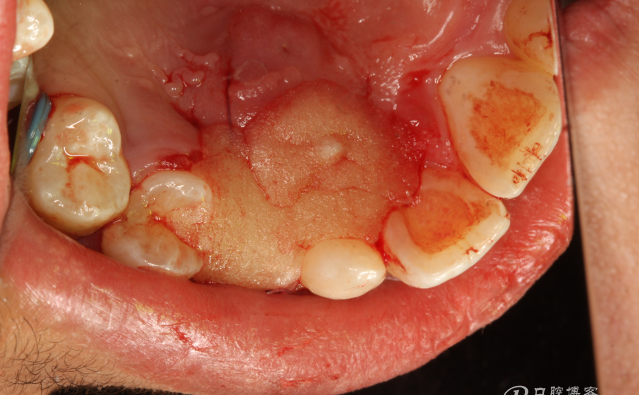

圖11.從乳尖牙到13牙冠區(qū)域去皮質(zhì)骨化處理

圖13.上牙周塞治劑,兩周后復(fù)診。